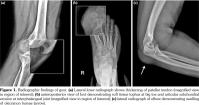

Gout is a clinical disorder resulting from urate crystal deposition.(1) Tendinopathy and enthesopathy are extra-articular gout manifestations. The common sites involved in knee are the popliteus tendon, cruciate ligaments, and quadriceps tendon.(2) Although patellar tendon has been mentioned as a possible involvement site, to our knowledge, only three case reports exist in the literature, two of which were reported in triathletes mimicking patellar tendonitis precipitated due to prolonged exercises.(3-5) In this article, we report a 34-year-old male patient with eight years history of gout who presented with one week history of pain and swelling of extremities. He underwent excision of the olecranon bursae and biopsy from the tophus involving first toe three years ago. Recurrent gouty attacks were treated with nonsteroidal anti-inflammatory drugs, colchicines (1 mg/day), and analgesics. Serum uric acid level was 11.9 mg/dL, C-reactive protein was 18.2 mg/dL. Allopurinol had been discontinued due to elevated liver enzymes (alanine transaminase: 132 U/L; aspartate aminotransferase: 85 U/L). Physical examination demonstrated tophi overlying the toe, and tenderness over the caudal aspect of patella. The patellar tendon was slightly thickened on radiographs. Soft tissue tophus at the interphalangeal joint causing adjacent

erosive changes, and swelling of olecranon bursae were seen (Figure 1). Magnetic resonance imaging showed fusiform mass-like thickening of the proximal patellar tendon, measuring 30x16 mm, with intermediate signal on T1 weighted and T2 weighted images. Edema of the tendon at insertion and patellar cortical irregularities not seen on radiograms were demonstrated (Figure 2).